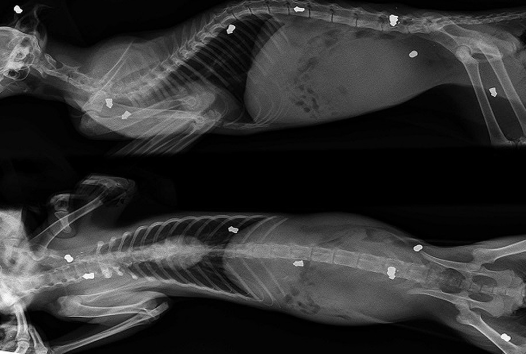

Котенок, в которого стреляли 9 раз стал ходить!

История несчастного котенка, которого нашли волонтеры в г. Березники шокирует. Малыш практически не шевелился и не двигался. Когда его привезли в ветеринарную клинику, то врачи ужаснулись - в него было выпущено девять пуль из пневматического пистолета, две из которых оказались в позвоночнике. Пришлось котенка срочно оперировать.

Выяснилось, что два раза стреляли живодеры в упор. Остальные пули стали следствием того, что котенок пытался уползти.

Малыша назвали Патрон (символично). Пока он живет на передержке у неравнодушного зоозащитника. Когда котенок поправиться, ему будут искать дом. Сейчас многие пристально следят за его жизнью, переживают:

"Ходит наш мальчик? Встал на ножки? Слезы радости на глазах! "

Даже после пережитых событий Патрон остался дружелюбным, добрым и игривым. Он с радостью мяукает при виде человека, трется об руки.